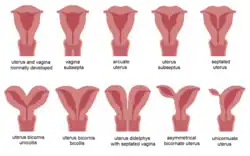

| Malformations of the uterus in humans | |

The American Fertility Society (now American Society of Reproductive Medicine) Classification distinguishes:

- Class I—Müllerian agenesis (absent uterus).

- Class II—Unicornuate uterus (a one-sided uterus).

- Class III—Uterus didelphys, also uterus didelphis (double uterus).

- Class IV—Bicornuate uterus (uterus with two horns).

- Class V—Septated uterus (uterine septum or partition).

- Class VI—DES uterus.

An additional variation is the arcuate uterus where there is a concave dimple in the uterine fundus within the cavity. The distinction between an arcuate uterus and a septate uterus is not standardized.